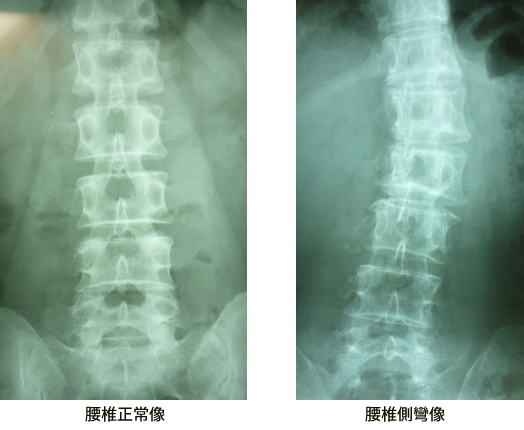

静力学的側弯

何らかの原因『足指、膝の骨折、捻挫』等の一方の下肢短縮による骨盤の下側下降の結果として発生する側弯を云います。

左脚が短縮して骨盤が左に傾斜する場合、脊柱は左に偏り体は左方向に倒れる傾向がありますので頭部の重心線を骨盤軸の中央に垂直にするためには腰椎が左凸側弯を起こし脊柱上部が右方向に倒れるのを防ぐために胸椎において代償作用により右凸側弯が生じます。

静力学的側彎

腰椎左5番が過骨化があります。

代償作用として胸腰移行部に回旋が見受けられます。

腰椎を左に傾斜した仕事が原因だそうです。

変形があるものの比較的症状も安定しています。